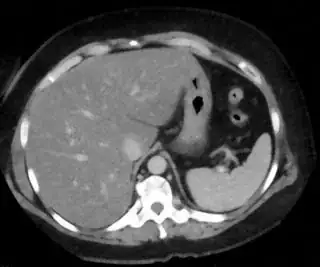

Below I apply two successive morphological openings to the image using a 3x3 circular kernel, and then apply k-means clustering to the gray levels. From your sample images and some I found on the internet, I decided to set k = 4. If you are using high-resolution images, first downsample them to dimensions ~400-600. Otherwise the morphological operation may not have a significant effect, and the k-means will be slow.

Below are some of the opened and segmented images. Of course there's more to be done in terms of

- separating out the liver region

- generalizing this to a large dataset

but hope this is at least a starting point.